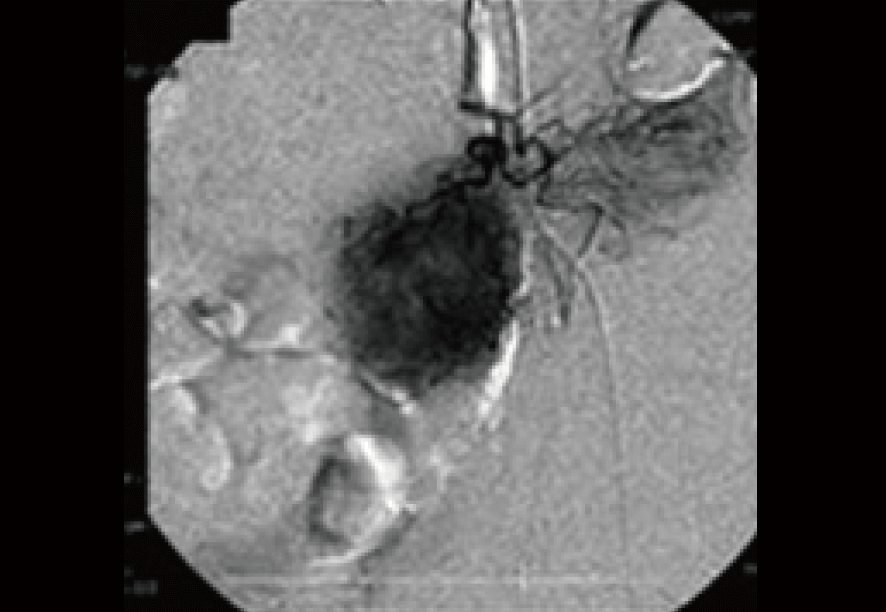

血管カテーテルによって大腸がんそのものを調査した画像。

がん細胞の回りを取り囲むがんの新生血管が良く観察できる。(丸く、黒々と染まった部分)

この時点での残り余命判断は非常に厳しいものであった。およそ1ヶ月程度。それも大きな急変が無ければ、が条件である。

即時入院、そして生存して病院を退院することが想定されない、非常に末期的状況とさえ言える状態であった。